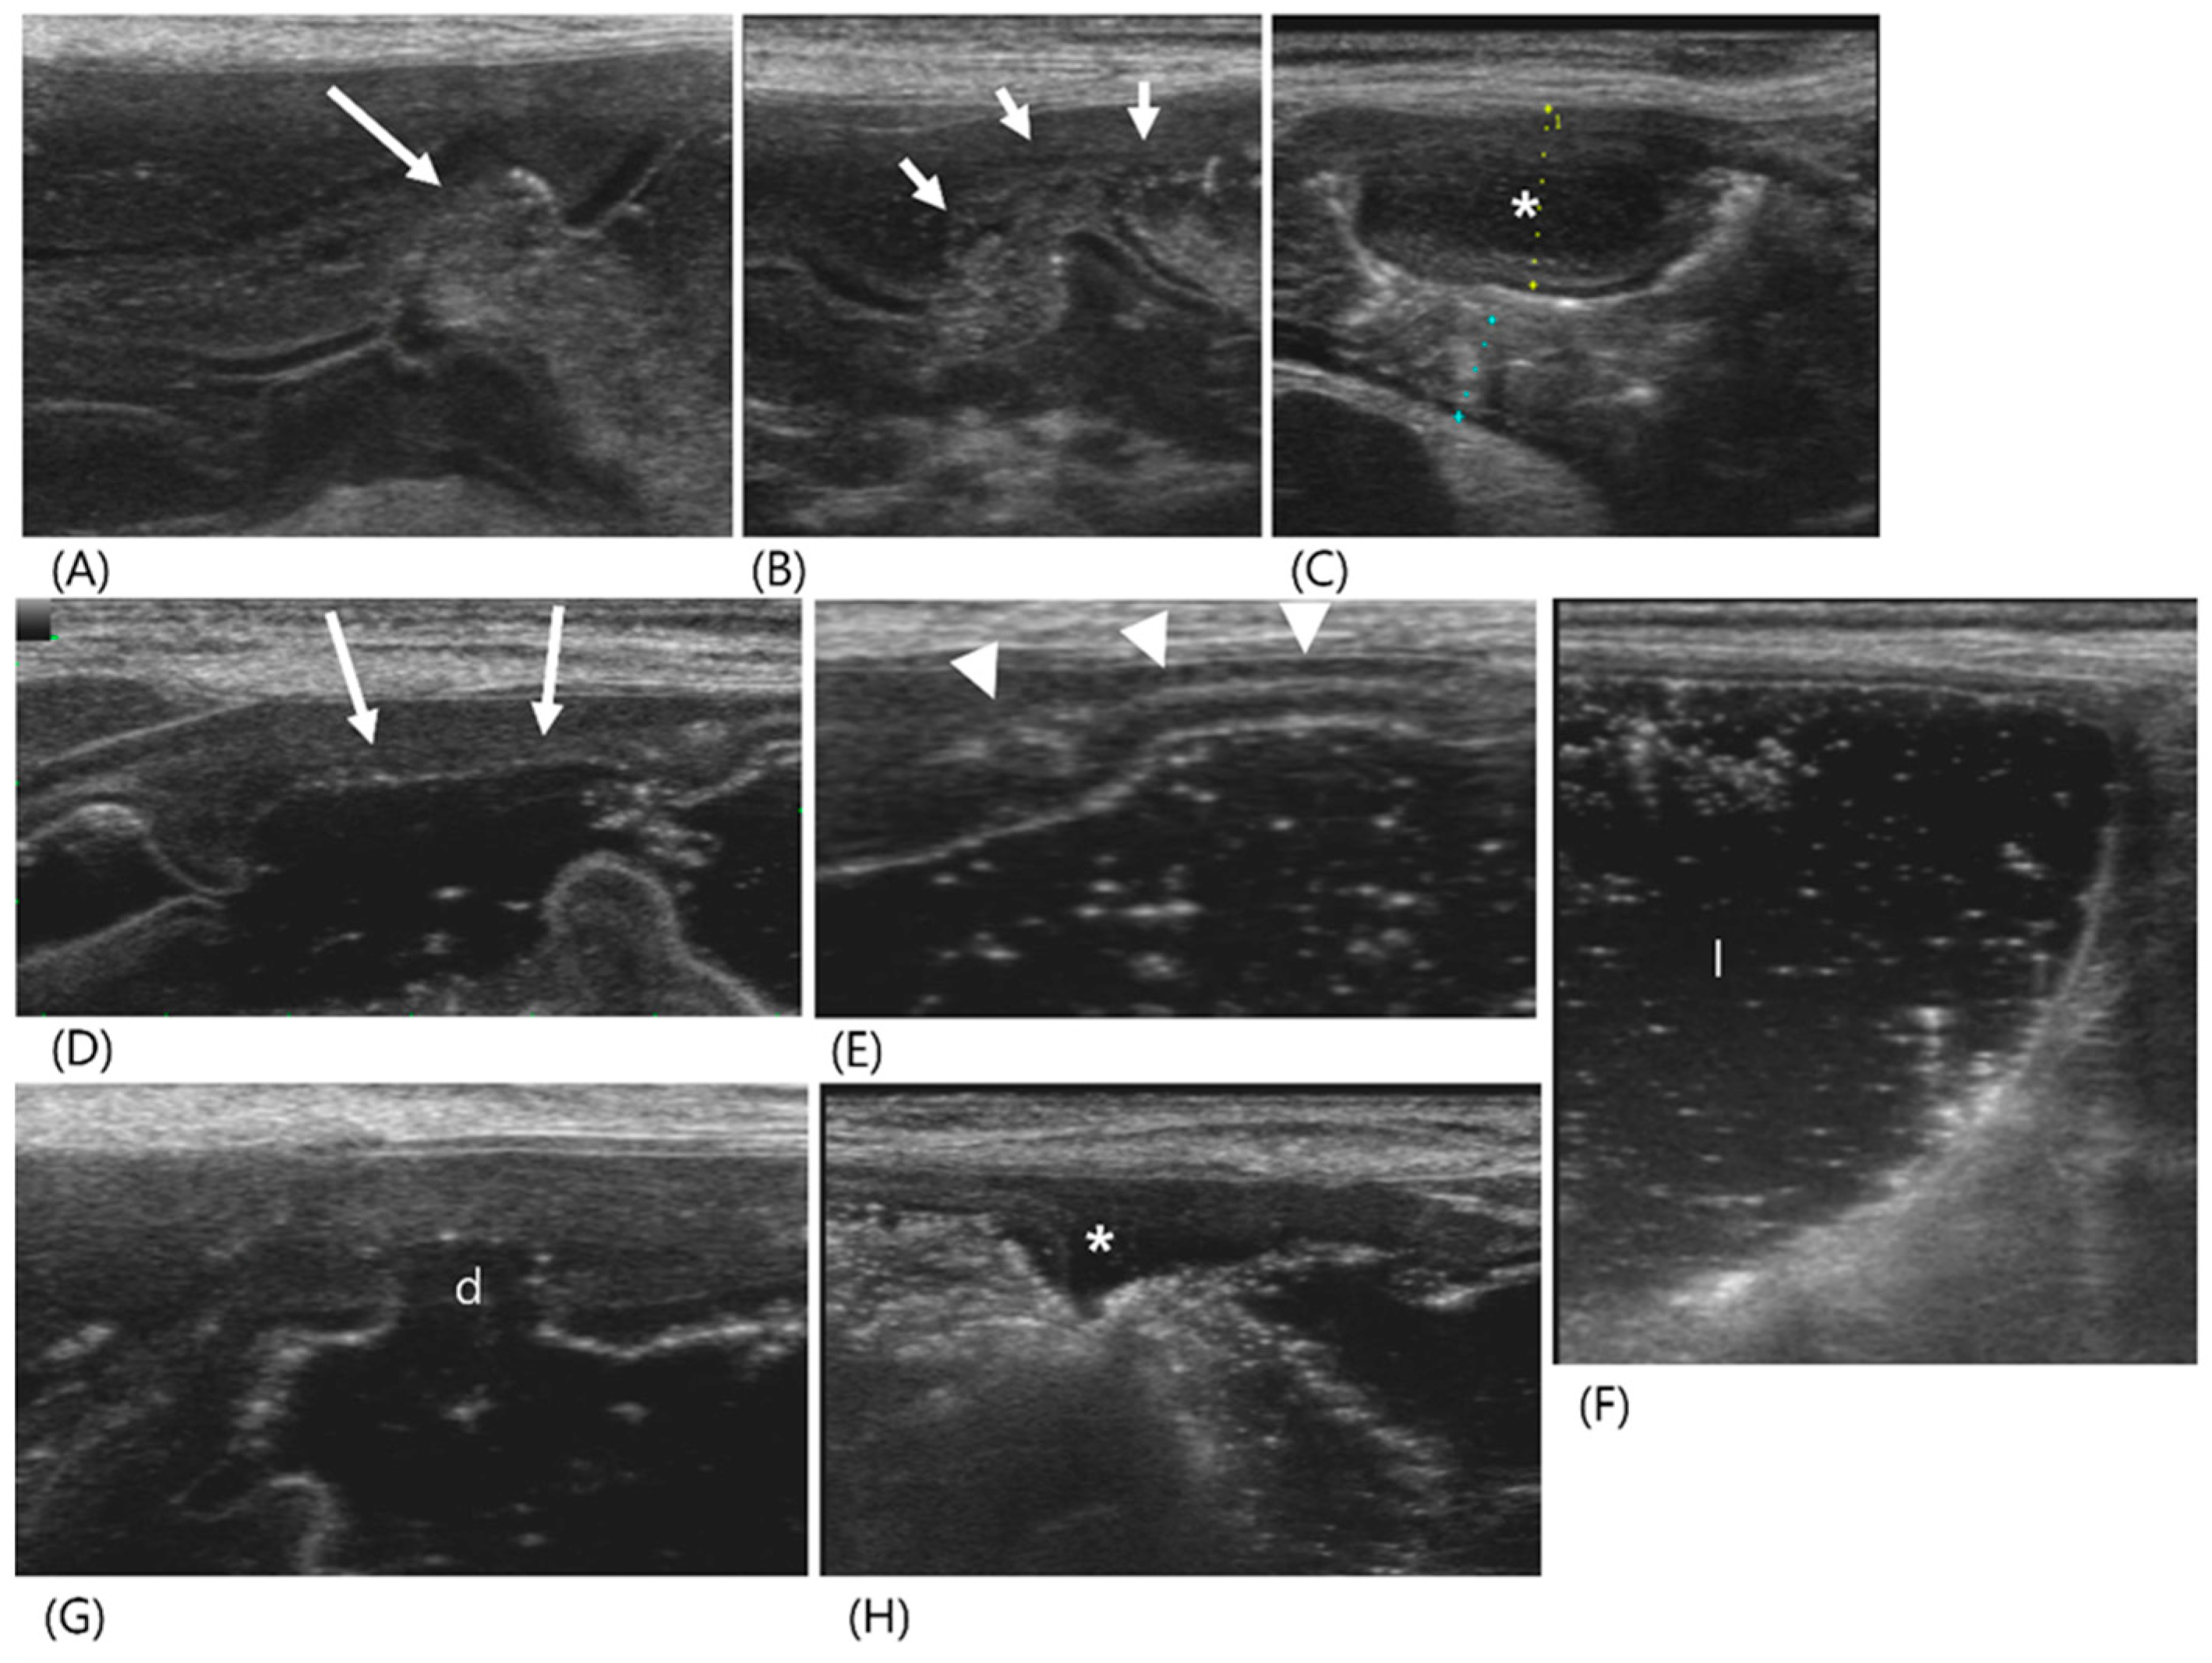

2.1. Case 1